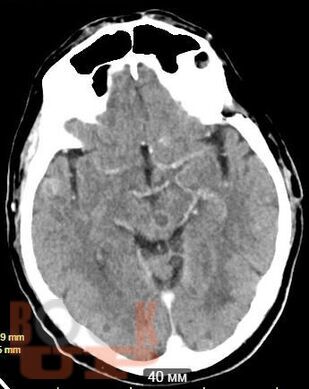

Учебное пособие освещает вопросы многоочагового поражения головного мозга. Рассматриваются различные нейрохирургические и неврологические заболевания с очагами поражения головного мозга в количестве более двух, такие как опухоли головного мозга (первичные и метастатические), воспалительные заболевания, демиелинизирующие заболевания, паразитарное поражение и другие патологии. В книге приведены алгоритмы дифференциальной диагностики данных заболеваний, начиная от особенностей клинической картины до специфики изменений сигнала в разных режимах МРТ. Также обозначена тактика ведения и прогноз заболеваний.